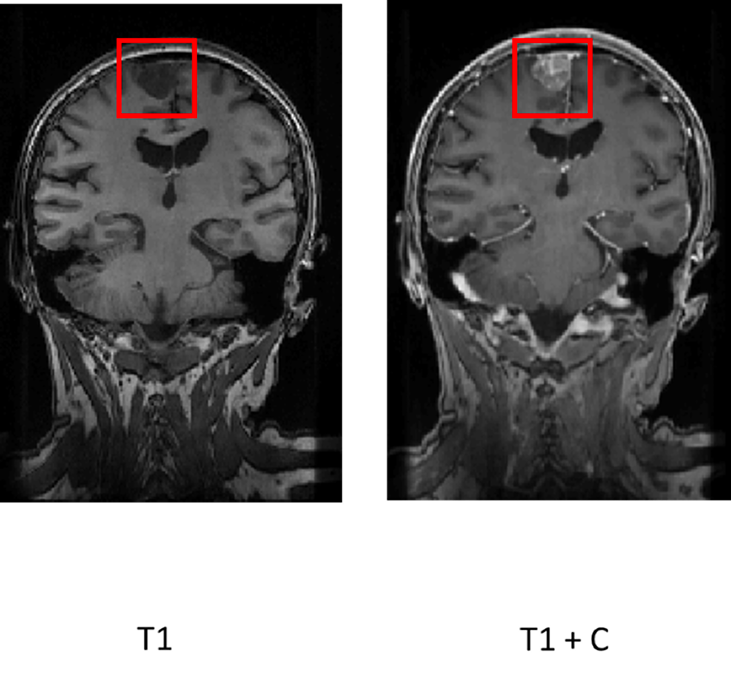

At CNSLab, analyses based on perfusion curves obtained from DSC (dynamic susceptibility contrast) recordings are conducted to assess perfusion in selected brain areas. Below are the results from a patient with a lesion visible on the T1 image, which enhanced after contrast administration.

Region of Interest for pMRI Analysis in the Selected Patient: T1-weighted images before and after contrast administration are shown.

The contrast agent concentration curve was analyzed for both the tumor and a control area that did not show contrast-related enhancement. A high K2 value, which measures leakage of the agent, indicates perfusion disturbances in the region of interest.

Results of the pMRI Analysis of Contrast Concentration Curves: The orange curve represents the tumor, and the blue curve represents the control area. The K1 and K2 values represent perfusion and contrast leakage effects, respectively.